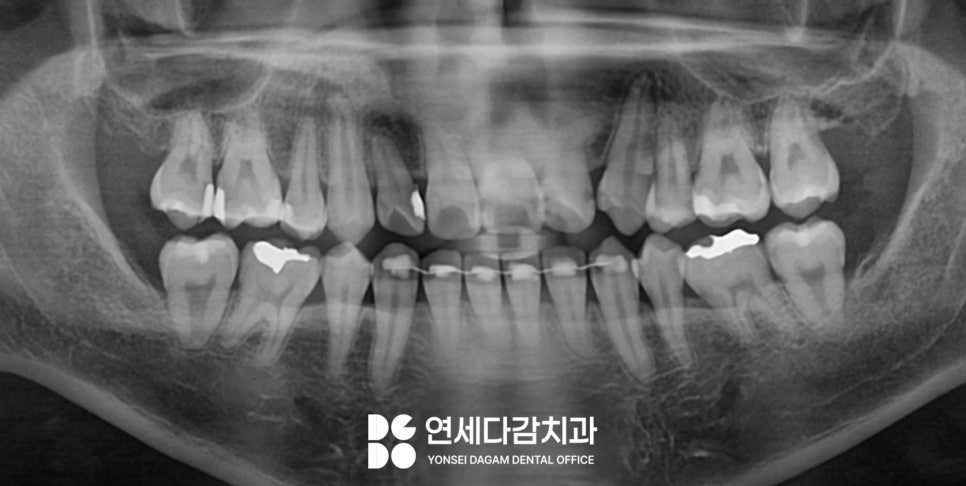

매복된 경우 오금역 치과 에서는

잇몸을 절개하고 난 뒤

주로 두 가지 방식으로 진행됩니다.

치아 통째로 빼는 방법.

첫 번째 방법으로 무사히

뺄 수 있었습니다.

이를 뺀 후에는 해당 부위를

봉합사로 꿰매고 마무리하게 됩니다.

나머지 사랑니도 위와 같은

방법으로 진행하였으며,

아래턱에 위치한 경우는

분할하는 방법으로 시행했습니다.